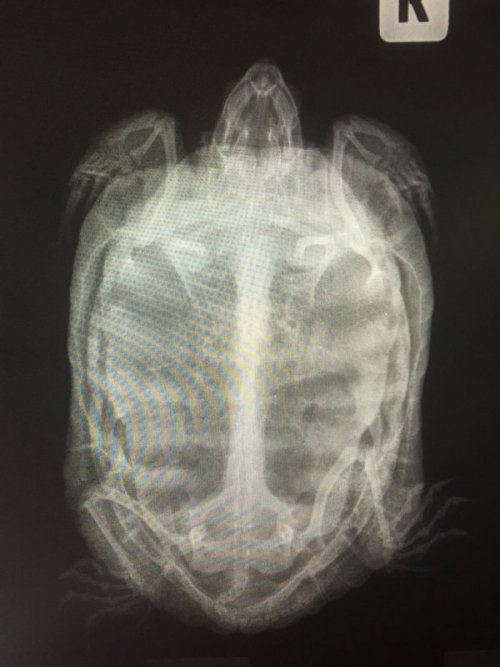

Dmitrii Ваше имя: Дмитрий Локация: Россия. Благовещенск Амурская область Опубликовано: 6 января 2021 Автор Опубликовано: 6 января 2021 Здравствуйте. снимки сделал. Сказали вздутие желудка. Я скину фото снимков. Сами снимки делают только на диске, я найду сидиром и скину по почте, напишите куда скинуть.

Консультанты moth Ваше имя: Мария Локация: Москва Опубликовано: 6 января 2021 Консультанты Опубликовано: 6 января 2021 @Dmitrii Через 5 дней после начала кальция, начать вводить метоклопрамид по 0,06 мл, подкожно (передняя лапа) 2 раза в сутки , курс 5 дней и если есть возможность купить препарат «серения», то по 0,2 мл, подкожно (передняя лапа) , 1 раз в 24 часа, 5 дней Кальций вводить ежедневно 7 дней, затем раз в 48 часа, курс 10 инъекций, далее раз в 72 часа, курс 10 инъекций и далее раз в 96 часов, курс 15 инъекций. Дозировка не меняется.

Dmitrii Ваше имя: Дмитрий Локация: Россия. Благовещенск Амурская область Опубликовано: 6 января 2021 Автор Опубликовано: 6 января 2021 Скажите, что за диагноз и это серьёзная болезнь? эспумизан ненужно давать? массаж вибрациями делать пока все уколы не закончу? После вибраций вздутие немного уменьшилось, но еду всё равно не ест. Рот открывает будто сейчас стошнит. Подскажите сколько он без еды протянет? А то он сильно похудел.

Консультанты moth Ваше имя: Мария Локация: Москва Опубликовано: 6 января 2021 Консультанты Опубликовано: 6 января 2021 @Dmitrii когда начнёте новые препараты - предлагать еду в это время каждый день всё подряд - рыбу, сырую курицу, сырую говядину, креветку, всё что угодно (кроме жирного мяса) - лишь бы начала есть. 2 месяца без еды вне спячки для черепахи очень плохо. Её выздоровление зависит от того развился уже паралич/парез или нет. Изначально всё началось из-за метаболических нарушений из-за дефицита кальция. Прогнозов врач дать не может, т.к. ситуация у Вас сложная и всё зависит от того есть у черепахи ещё внутренние ресурсы восстановиться или нет, произошли уже необратимые изменения или нет.